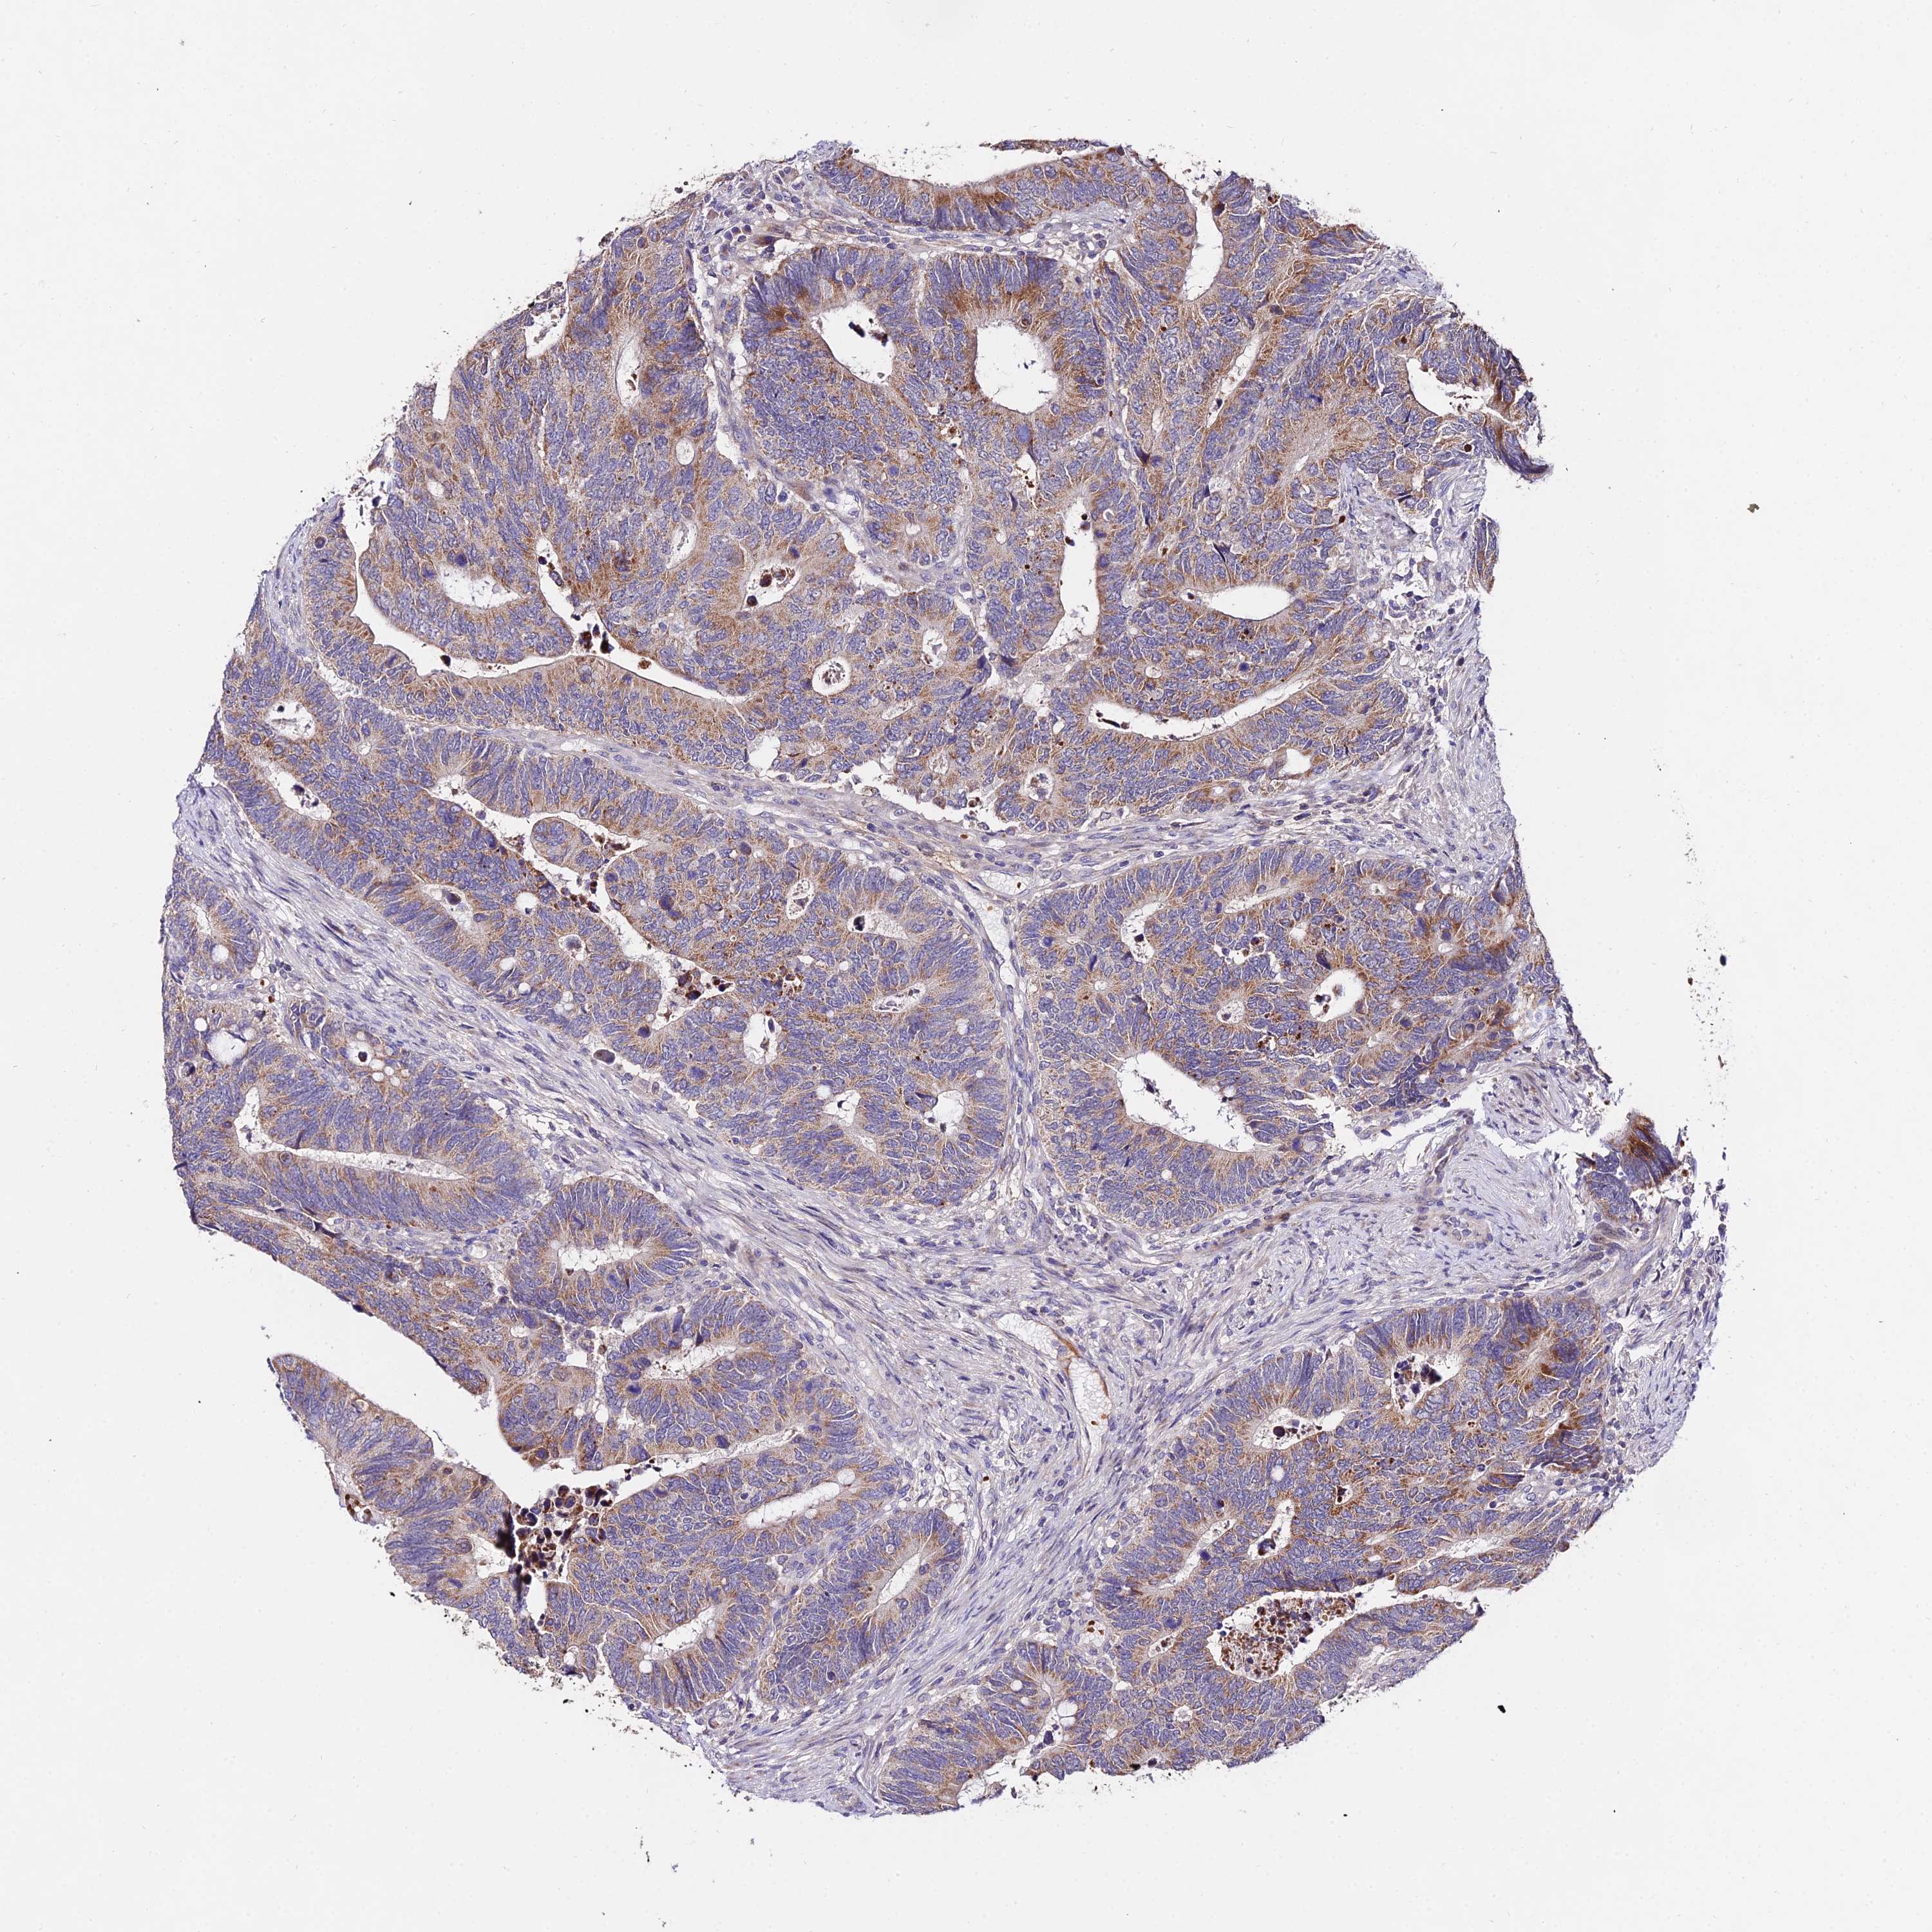

CANCER COLORECTAL CANCER Show tissue menu

Colorectal cancer

Human cancer

Rectum adenocarcinoma